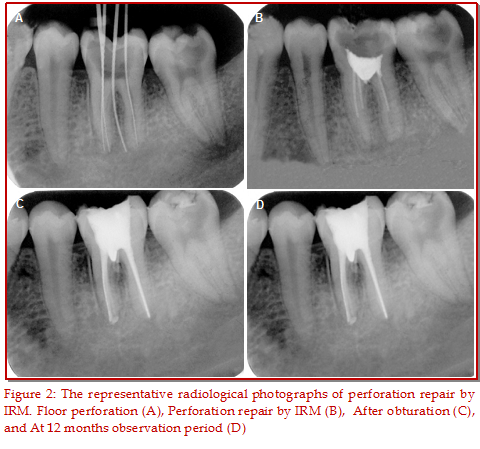

The purpose of the present study was to assess the clinical and radiological outcome following repair of furcal perforation by mineral trioxide aggregate (MTA) and intermediate restorative material (IRM) in mandibular molar teeth. Forty teeth having furcal perforation were enrolled in this study, out of which 20 teeth were treated with MTA and the remaining 20 teeth were subjected to IRM treatment. Following perforation repair, all teeth were subjected to root canal treatment followed by final restoration. Clinical and radiological outcome was evaluated at 3, 6 and 12 months interval. The results showed that in both MTA and IRM groups, pain, tenderness on percussion as well as swelling and sinus was gradually decreased with the increase of the observation period. Furthermore, the widening of the periodontal ligament space and communi-cation with the oral cavity were gradually decreased. Although there was no significant differences between MTA and IRM at 3 and 6 months observation period but at 12 months, the clinical outcome between MTA and IRM was statistically significant (p<0.05). It can be concluded that repair of furcal perforation by MTA showed more effective than that of IRM.